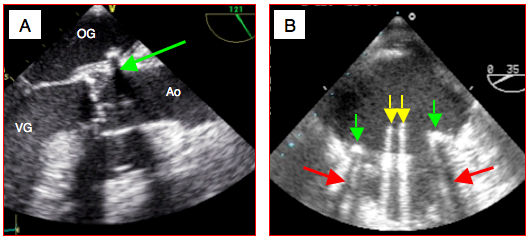

Figure 25.42 : Ombres. A: calcification de la racine de l'aorte (flèche verte) en vue long-axe 120°; elle crée un cône d'ombre distal qui apparaît comme un fuseau noir. B: artéfacts liés à une prothèse mitrale St.Jude; l'anneau métallique (flèches vertes) crée un cône d'ombre (flèches rouges); les ailettes en pyrolocarbone (flèches jaunes), qui sont en position ouverte (diastole), semblent se prolonger sur tout l'écran alors qu'elles mesurent moins de 1.5 cm.